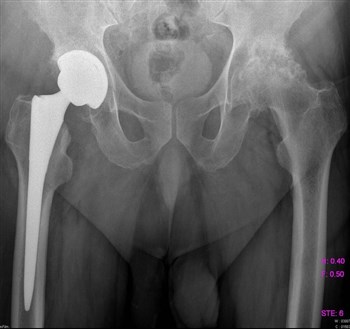

Артроз тазобедренного сустава

Все чаще и чаще пациенты обращаются с жалобами на боли в паху, в колене, иногда на боль в ноге, на скованность движений, нарушение походки.

Как правило, страдают таким недугом женщины после 40 лет.

Боль локализуется в вышеуказанных местах как на одной, так и на обеих ногах.

Для того, чтобы поставить верный диагноз, проводят диагностику, которая включает:

- МРТ;

- Рентгенографию;

- Компьютерную томографию.

Проведенная диагностика покажет, в какой стадии находится заболевание, будет дана точная информация о состоянии мягких и костных тканей.

Если заболевание не в хронической форме, или, проще говоря, не запущено, то лечение происходит обычным парацетамолом, без какого-либо хирургического вмешательства. Лечащий доктор назначает курс массажа, лечебной гимнастики, постоянный контроль ортопеда. При ноющих болях прописывается курс болеутоляющих – Кеторол, Диклофенак.

Асептический некроз головки бедра

Все симптомы примерно те же, что и при других заболеваниях, связанных с суставами. Все же важным отличием является постоянная неутихающая боль в бедре, атрофия мышц, укорочение конечности, хромота.

Асептическому некрозу головки бедра подвержены мужчины, особенно после травм – перелома, вывиха или хирургического вмешательства, так как повреждаются сосуды, кровь проходит хуже и они закупориваются тромбами.

В зависимости от запущенности болезни, проводят медикаментозное или хирургическое лечение.

Медикаментозное лечение проводится в том случае, если нет признаков разрушения кости и уровень кальция в организме в пределах нормы.

Хирургическое вмешательство показано при острой форме заболевания или если медикаментозная терапия не дала положительных результатов.